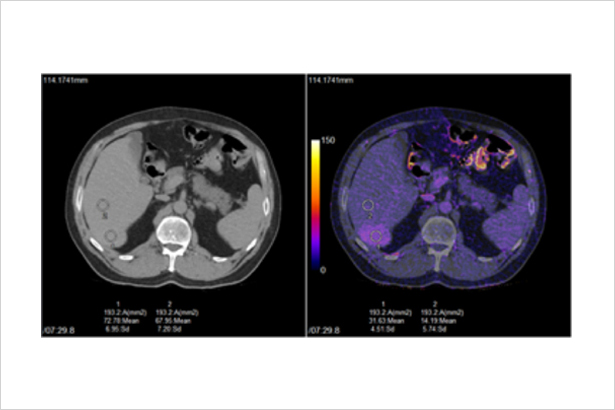

秉承佳能醫療超高端640層CT的AI同步軌道掃描技術與柔性掃描與彩色成像技術,在不增加掃描代價和患者輻射劑量代價的前提下,利用平掃和增強數據進行柔性的器官配準,0鍵式地得到彩色碘圖等有價值的診斷信息,更敏感地發現病灶和淹沒在器官背景的微小血供變化。

在柔性彩色體部成像下,淹沒在器官背景中的強化,可以在彩色碘圖下,顯著地表達出來。